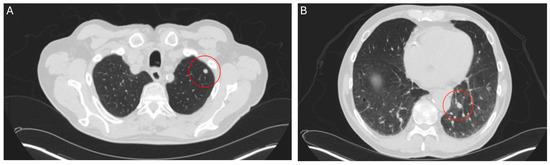

Figure 1.

CT thorax scan, 27 May 2024, before commencement of treatment with belzutifan: pulmonary metastases for the left-upper (A) and lower lobe (B).